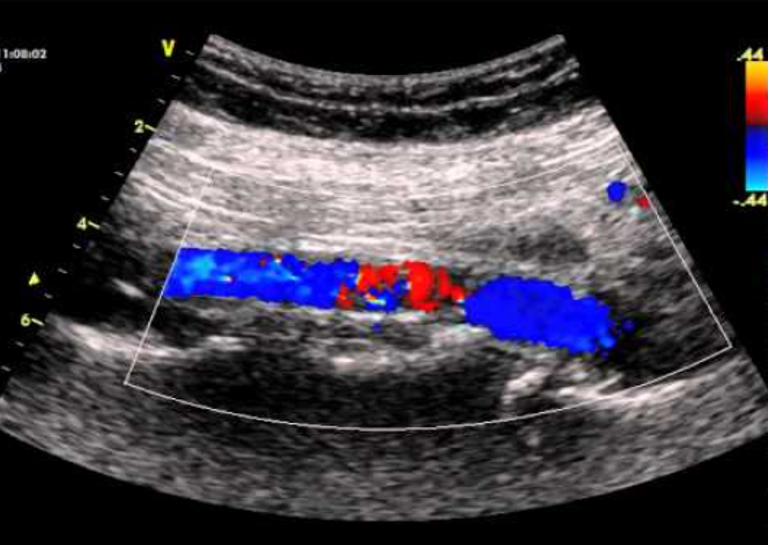

Abdominal Aortic Aneurysm (AAA) 30 minutes

•  Aneurysms

Whole body ultrasounds provide a non-invasive, painless, imaging option, allowing for the assessment of various organs without exposure to radiation.

This screening can help identify abnormalities such as tumors, cysts, or vascular issues at an early stage, potentially improving treatment outcomes. Our general screening exams include: breast, thyroid, kidneys, liver, spleen, aorta, pancreas, and calf veins.